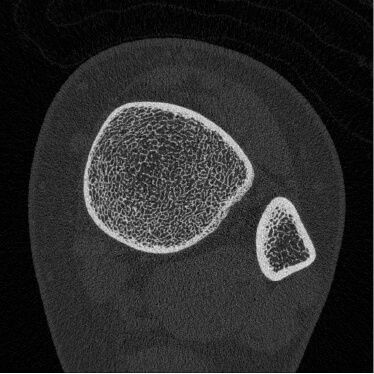

HR-pQCT装置(高解像度の末梢骨用の定量的CT装置)

高解像度末梢骨用定量的CT(high-resolution peripheral quantitative CT:HR-pQCT)は,前腕や下腿の骨を高解像度で撮影し、骨の内部構造を三次元的に評価することができる最先端計測機器です。従来の骨密度検査(DEXA)では評価しきれなかった、「骨の質」や骨の細かい構造の変化を捉えることができ、より高度な骨粗鬆症の診断・治療効果の判定に役立ちます。HR-pQCTは研究機関や専門病院など、限られた施設でしか導入されておらず、先進的な骨の評価を受けられることが当院の強みのひとつです。大学や研究機関とも共同研究を行っています。実際に患者さんの骨の状態を詳しく評価し、テーラーメードの骨の治療を行うようにしています。

【撮影画像】

-

手関節部

(20代) -

手関節部

(50代骨粗) -

足関節部

(20代) -

足関節部

(60代骨粗)